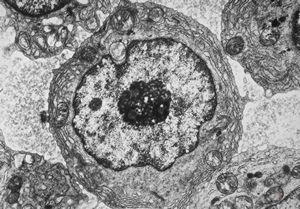

M,62y. | bone marrow - plasmocytoma

M,64y. | bone marrow - plasmocytoma

M,62y. | bone marrow - plasmocytoma - inclusions